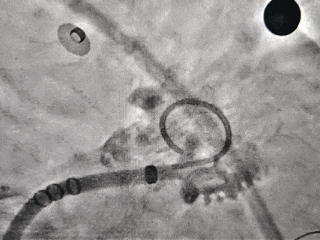

DSA造影+测量

DSA下心耳开口29.7mm,深度23mm;

-

综合测量结果,选择MemoLefort LAFDQ-32封堵器进行对共干区域进行封堵。